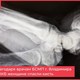

20 сентября 2023 в 13:05 Владимирские врачи выходили недоношенную малышку весом меньше двух килограммов

Из отделения патологии новорожденных и недоношенных детей №2 владимирской ОДКБ выписана очередная малышка. Когда девочка родилась, она весила всего 1,8 килограмма, - за ее здоровье врачам пришлось побороться.